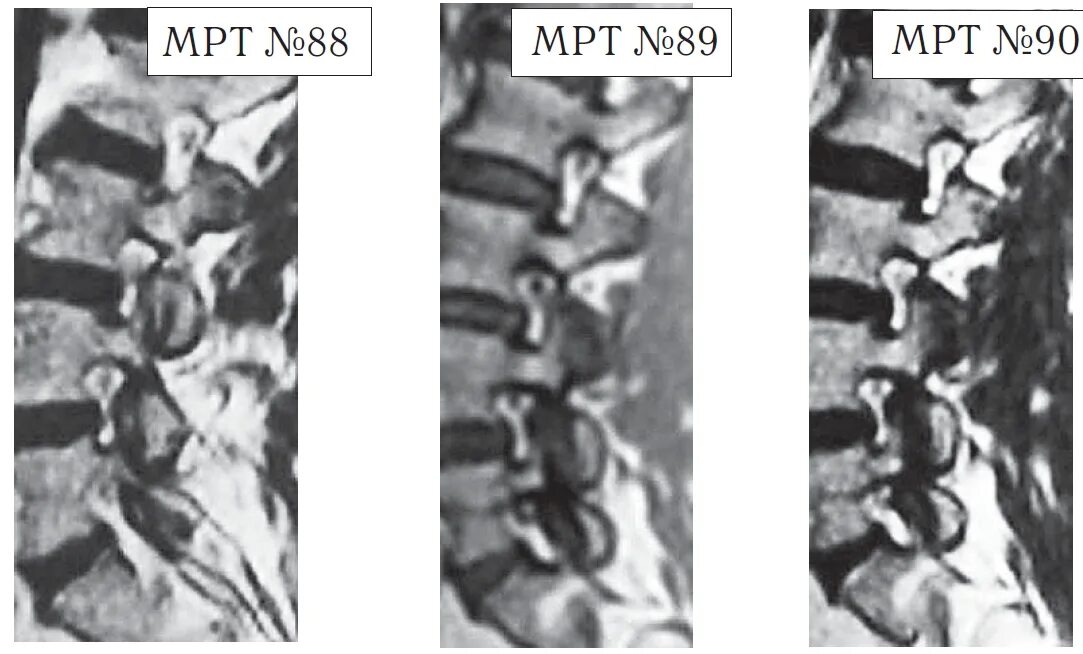

Спондилоартроз на уровне l1 s1